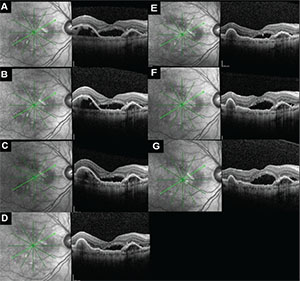

| Figure 6. After the addition of dorzolamide-timolol to monthly ranibizumab regimen, optical coherence tomography (OCT) images in another subject at enrollment (A), week four (B), week eight (C), week 12 (D) and week 16 (E) show a gradual decrease in subfoveal subretinal fluid (SRF) as well as pigment epithelial detachment on the left side of the images. Dorzolamide-timolol was discontinued after week 16 and the patient continued to receive monthly intravitreal ranibizumab only. The subsequent OCT images at week 20 (F) and week 24 (G) demonstrate increasing SRF after stopping the drop. Prior to enrollment, this patient had received 30 ranibizumab injections. |

In addition to the decrease in CST (Figure 2), mean maximum SRF height also decreased from 126.6 μm at enrollment to 49.5 μm at the final visit (P=0.02) with the decrease also noted at the first visit after enrollment (Figure 3). Moreover, all study eyes experienced a decrease in maximum SRF height at the final visit. Additionally, four out of the 10 study eyes demonstrated complete resolution of SRF by the final visit.

Additionally, the study design does not allow us to determine whether the observed effects were due to the independent action of dorzolamide vs. timolol rather than the combination of dorzolamide-timolol. Another limitation was the lack of a control group and the possibility that our findings represent normal fluctuations of the disease. However, this is unlikely as we only included patients who had persistent exudation over six months prior to inclusion despite fixed-interval anti-VEGF injections. In fact, the mean CST, SRF and PED heights at the visit prior to enrollment